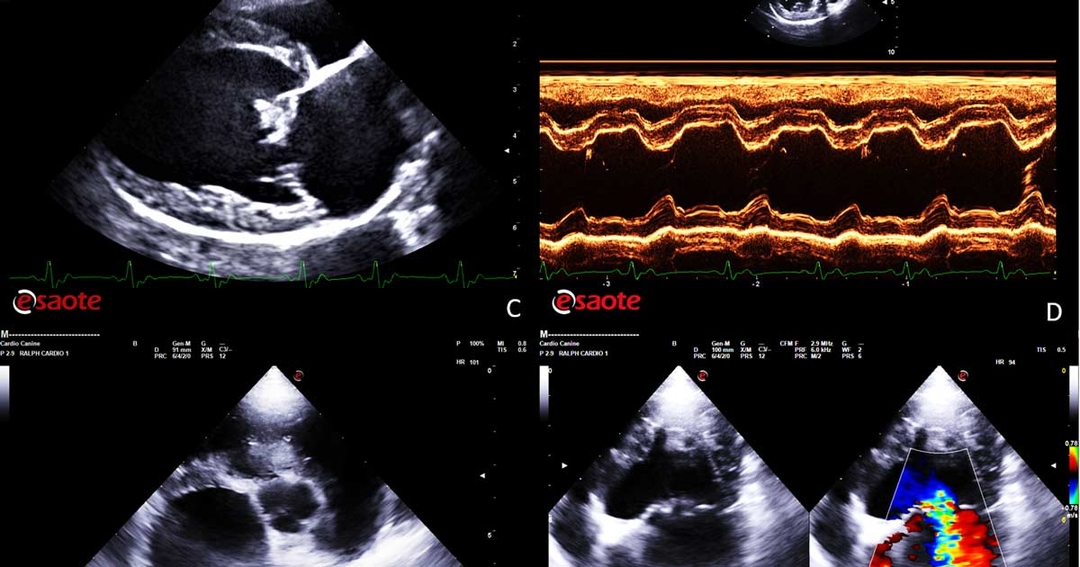

However, a definitive diagnosis requires a full echocardiographic examination with colour and spectral Doppler to confirm the presence of mitral regurgitation (MR).

The main structural echocardiographic lesion associated with MMVD is characterised by thickening and distortion of the valvular leaflets and chordae tendineae, usually more pronounced at the level of the anterior mitral valve leaflet. The thickness and irregularity of the valvular leaflets tend to become more prominent during disease progression.

From a functional point of view, the main features of MMVD on B-mode (2D) echocardiography are the flattening of the mitral valve leaflets and their systolic prolapse, which is confirmed on echocardiography by observing one or both leaflets bending back towards the left atrium during systole.

Superimposition of colour flow Doppler (colour flow mapping [CFM]) at the level of the mitral valve will reveal the presence of systolic valvular regurgitation caused by the incomplete or inefficient apposition of the valvular leaflets.

Visualisation of valvular regurgitation on colour Doppler is characterised by the presence of a mosaic of colours caused by aliasing (an image artefact that occurs when the blood flow velocity exceeds the Nyquist limit) as blood rushes through the regurgitant orifice towards the left atrial lumen.

Many clinicians tend to activate the CFM in right parasternal four-chamber long axis view. However, the correct alignment for any Doppler assessment, including CFM, should be parallel to the blood flow; therefore, the best position to detect MR is the left parasternal four-chamber apical view.

This view will also allow a better visualisation of size and direction of the regurgitant flow, and a correct alignment of the spectral Doppler that can be used to estimate the pressure gradient between the left ventricle and the left atrium in systole.